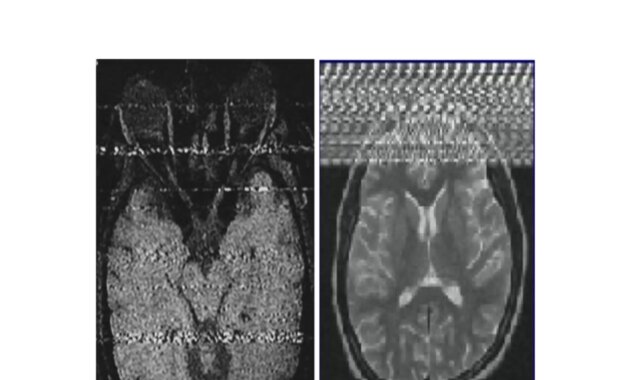

One of the most common types of MRI artifacts is the motion artifact. Imagine a patient unable to remain still during the scanning process. The motion can blur the resultant images, rendering them less diagnostic. Such blurring can mislead radiologists, potentially leading to incorrect interpretations or misdiagnoses. Patients often wonder: How can a slight movement affect such a sophisticated technology?

Moreover, equipment-related artifacts may arise from improper settings or malfunctioning hardware. For instance, certain MRI sequences may not be optimally configured, leading to issues like chemical shift artifacts, which occur when fat and water resonances create mismatched signals. Radiologists face challenges identifying the true pathology amidst these unwanted signals. Thus, how do they discern between an artifact and a genuine pathological finding?